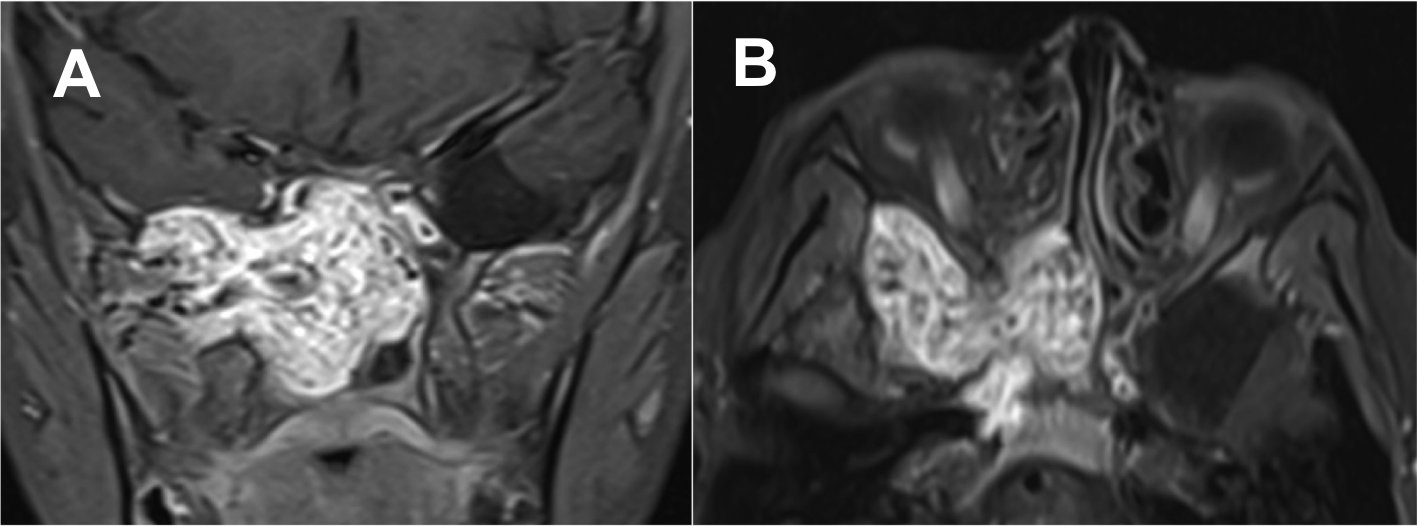

Introducción: La cirugía endoscópica endonasal se ha convertido en una herramienta fundamental para el manejo de patologías que comprometen la base de cráneo. En casos bien seleccionados, estas técnicas permiten resecciones quirúrgicas con una menor morbilidad sin comprometer los principios oncológicos de resección. Con el desarrollo de instrumental especializado, nuevas tecnologías y la experiencia de los cirujanos, la cirugía endoscópica endonasal se usa cada vez más en cirugía de base de cráneo en niños.

Diseño: Estudio observacional descriptivo de tipo serie de casos. Metodología: se describe la experiencia con pacientes pediátricos llevados a cirugía endoscópica endonasal para manejo de tumores de base de cráneo en el Instituto Nacional de Cancerología entre julio de 2014 y diciembre de 2016.

Resultados: Fueron intervenidos 8 pacientes entre los 2 y 14 años, con una edad promedio de nueve años y un seguimiento promedio de 16 meses. En el 75% se hizo una resección total del tumor. Un paciente requirió una reintervención y un paciente fue sometido a radiocirugía post-operatoria. 1 paciente falleció a pesar de múltiples intervenciones, quimioterapia y radioterapia.

Conclusión: La cirugía endoscópica endonasal para tumores de base de cráneo puede ser utilizada de forma segura en los pacientes pediátricos, es una técnica que en casos bien seleccionados pueden ofrecer excelentes resultados disminuyendo la morbilidad y complicaciones de las técnicas abiertas.

Koutourousiou M, Gardner PA, Fernandez-Miranda JC, Tyler- Kabara EC, Wang EW, Snyderman CH. Endoscopic endonasal surgery for craniopharyngiomas: surgical outcome in 64 patients. J Neurosurg. 2013;119(119):1194–207.

Hernandez-Alarcón VJ, Hernandez-Gonzalez S. Nasoangiofibroma juvenil: una revisión actualizada del diagnóstico, clasificación y tratamiento. Acta otorrinolaringol. cir. cabeza cuello. 2011;39(3):147–57.

Zanation AM, Mitchell CA, Rose AS. Endoscopic Skull Base Techniques for Juvenile Nasopharyngeal Angiofibroma. Otolaryngol Clin North Am. 2012 Jun;45(3):711-30.